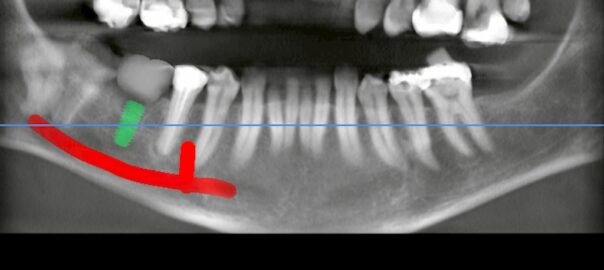

- 2025/09/06 左下欠損による傾斜歯とインプラント治療

こんにちは、静岡市駿河区石田の小嶋デンタルクリニックです。 本日は「左下の欠損部における傾斜歯への負担から抜歯に至り、インプラントで再構築した症例」をご紹介します。 症例背景と主訴 患者様は左下の奥歯に強い痛みを訴えて来 … 続きを読む 左下欠損による傾斜歯とインプラント治療